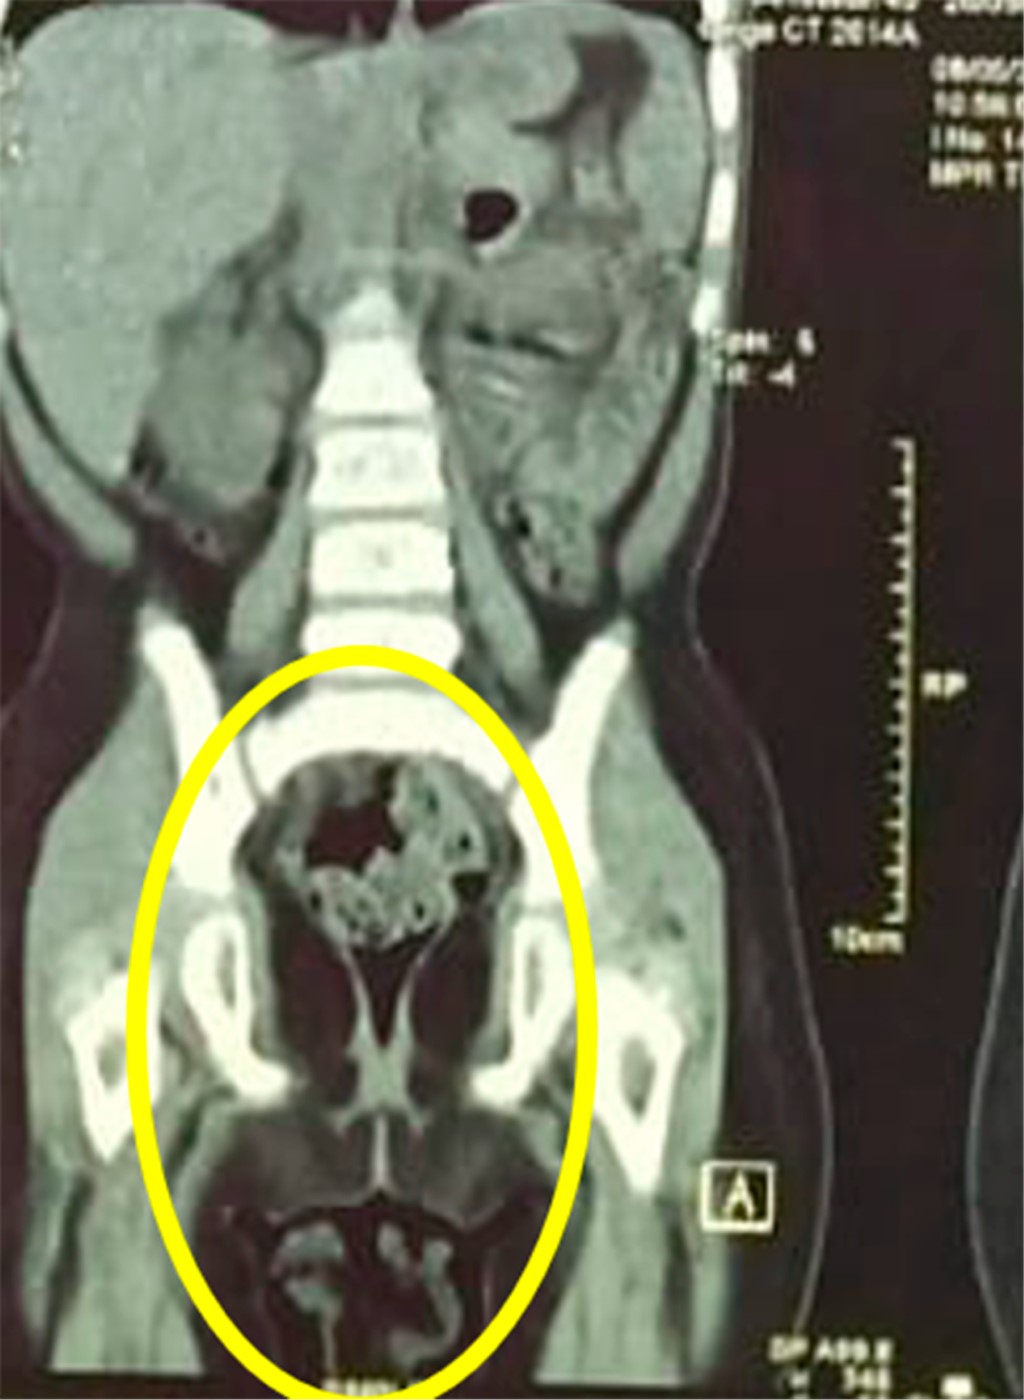

La paciente se hospitaliza para realizar tomografía; el estudio confirmó la presencia de una masa intravesical de 4 × 3 cm de diámetro y 5 × 3 cm de longitud, con lesiones hiperdensas con centros hipodensos (Figura 3); además se observaron ganglios linfáticos inguinales bilaterales de aspecto reactivo e hidronefrosis bilateral grado 2. Pero sin evidenciar metástasis a distancia (Figura 4).

Figura 3

Figura 4